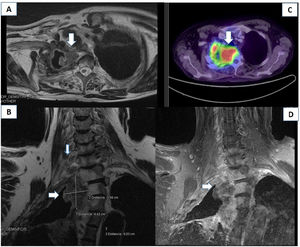

An electromyoneurography study revealed alterations to the superior and middle trunks of the brachial plexus (Fig. 1). A blood analysis detected hypercalcaemia (11 mg/dL) and hyponatraemia (117 mmol/L), which were asymptomatic. A head, neck, chest, and abdomen CT scan revealed irregular thickening of the apical-medial wall of the post-lobectomy cavity; the mass was polypoid and protruded to the lumen, involving soft tissue and eroding the adjacent bone structures. This finding is compatible with tumour infiltration to the T2–T3 intervertebral foramen (Fig. 2). An MRI study of the brachial plexus revealed tumour infiltration in the right brachial plexus at the level of the scalene triangle, with involvement of the nerve roots due to perineural invasion and proximity to the intervertebral foramina, particularly at C7–T1 and C6–C7, with involvement of the C7, T1, T2, and T3 vertebral bodies (Fig. 2). PET-CT revealed increased uptake in the cervical tumoural mass (Fig. 2), with no signs of dissemination to other areas. The cytological study of a bronchial biopsy sample revealed malignant cells (recurrence of lung epidermoid carcinoma, stage IIIB). The patient was started on chemotherapy and radiotherapy, but died 4 months later due to pneumonia.

(A) Lung CT scan showing a mass in the apex of the right lung, causing ganglion compression and T2 displacement and invasion. (B and D) An MRI scan of the right brachial plexus (coronal section, STIR and T1FSE sequences) showed a mass measuring 3.58 × 4.42 cm at the level of the lung apex and displacing the T1–T3 vertebral bodies, reaching the roots of the distal brachial plexus. (C) PET-CT scan revealing increased 18F-FDG uptake in the mass.